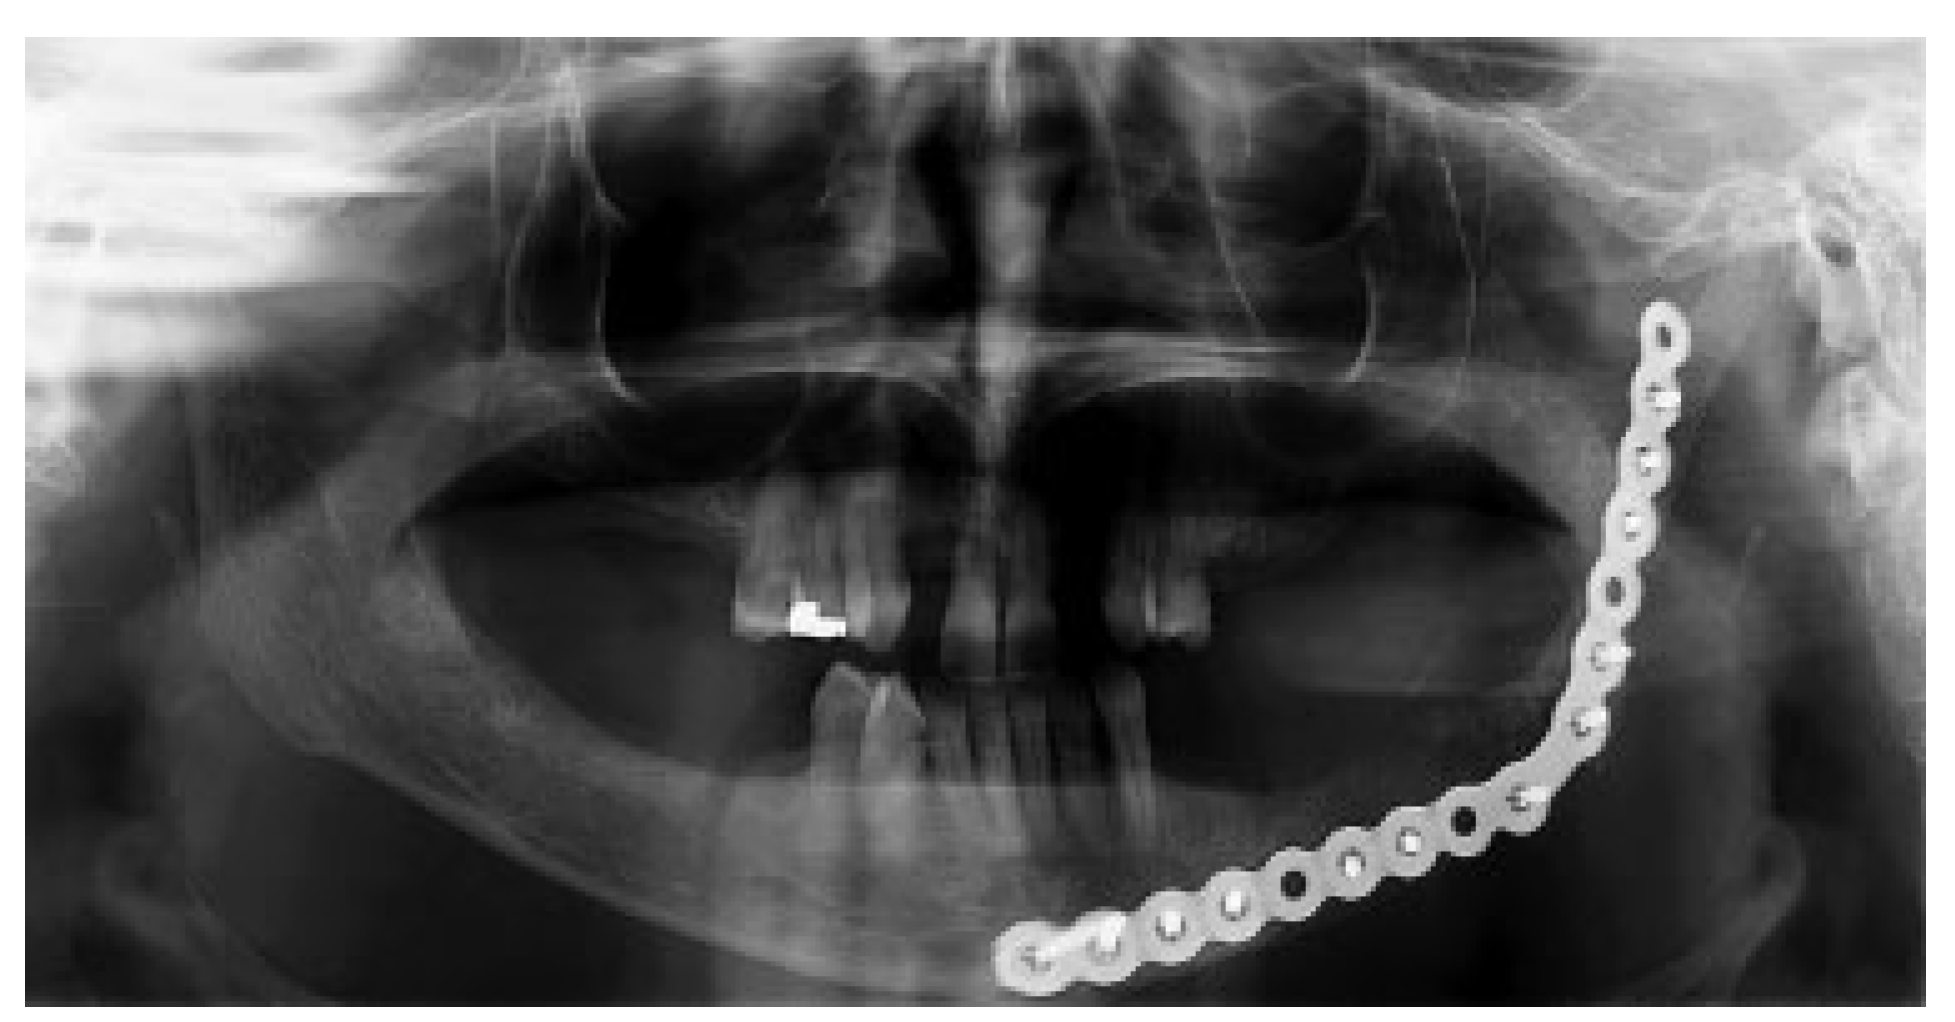

A 46-year-old Caucasian female presented to the Oral Surgery Department at Alameda County Medical Center–Highland General Hospital, complaining of dental pain in maxillary left region for 2 months. Her medical history was significant for hypertension and congestive heart insufficiency for which she takes enalapril, carvedilol, furosemide, and Klor-Con (Klor- Con®, Upsher-Smith Laboratories, Inc., Morristown, NJ) (potassium chloride). She is allergic to codeine. She has a 10 pack- year history of smoking and a remote history of methamphetamine use. Her past surgical history is significant for parathyroid carcinoma, which resulted in primary HTP. She reported that time weight loss, hives, insomnia, fatigue, and bone pain before surgical excision performed 17 years ago. No uterine or kidney lesions were present. She also reported that her brother had a jaw tumor, not surgically treated, because the “jaw growth stopped.” Unfortunately, her brother does not live in the city, and a better investigation concerning his disease could not be performed. Extraoral examination revealed a small swelling in the left mandibular border. Intraorally, the patient presented with poor hygiene with multiple extensive dental caries and periodontal disease. An asymptomatic and firm posterior left mandibular swelling was also present, with buccal and lingual expansion. Radiographic and computed tomography (CT) scan examination revealed a 5-cm mixed radiolucent and radiopaque image in the left mandibular body with well-defined borders and base expansion (Figure 1 and Figure 2a,b). An incisional biopsy was obtained with an intraoral approach which was diagnosed as a benign fibro-osseous lesion, consistent with ossifying fibroma. Initial laboratory analysis prior surgery showed a small increase in serum calcium of 10.5 mg/dL (8.4–10.2 mg/dL). Based on these findings and with the history of parathyroid carcinoma, the patient was referred to an endocrinologist. CT scan of the neck was unequivocal for recurrence and no correction of serum calcium was necessary. The association of ossifying fibroma with primary HPT due parathyroid carcinoma, with a family history of a similar jaw lesion, led to a high suspicion of HPT-JT syndrome. It was extensively discussed with the patient, but she refused to perform any genetic test. Our treatment planning initially included the extraction of the left inferior premolars, which had extensive caries lesions and mobility, performed before the lesion surgical removal. It would enable a better wound closure after resection. Three months later (2010 March), the ossifying fibroma was surgically resected with 5 mm margins (Figure 3) using an intraoral approach, and a 2.4-mm reconstruction plate was placed from the left mandibular ramus to the parasymphysis (Figure 4a–c). The postoperative course was remarkable only for neurosensory disturbance in the left inferior alveolar nerve, which improved but was not completely resolved after 3 years of follow-up. Seven months later (2010 October), using an extraoral approach, the patient underwent a left mandibular reconstruction using her left posterior iliac crest, as well as the right anterior iliac crest. The corticocancellous blocks were secured with 2.4 mm monocortical screws, while cancellous bone chips were inserted between the block grafts (Figure 5a–c). Although regular follow-ups were performed within the first 4 postoperative months, the patient recently returned to the oral surgery clinic for revaluation in 2012. Clinical and radiological examinations (Figure 6) were performed, and oral rehabilitation with dental implants was planned (June 2012). The patient subsequently underwent a third surgical intervention, under local anesthetic and intravenous sedation. The remaining maxillary teeth were extracted, followed by osteoplasty and placement of four implants: two anterior axially placed and two posterior tilted placed. At the same operating time, monocortical screws were from the mandible and three implants were placed in the region of teeth 20, 21, and 28, and alloplastic bone graft was placed covering the exposed threads of the implants (Figure 7a,b). A temporary superior and inferior prostheses were subsequently placed, and a period of 6 months for implant osseointegration before final prosthesis rehabilitation is being observed. The patient is currently followed regularly and, after 3 years of surgical resection, no evidenceof tumor recurrence is seen (Figure 8). Therefore, no evidence of parathyroid carcinoma recurrence is seen after 21 years of endocrinological follow-up.

In terms of treatment, complete excision is recommended although recurrences are uncommon, even after enucleation or curettage [27]. However, due to the mandibular base involvement, large buccal and lingual bone expansion and extensive mobility of the premolars in this case report prompted the decision of surgical resection of the lesion and placement of a 2.4-mm reconstruction plate from the left mandibular ramus to the parasymphysis to preserve the mandibular contour. Mandibular reconstruction with posterior and anterior iliac crest was performed in a second surgical intervention due the possibility of lesion recurrence, even uncommon.

Figure 4. (a) Panoramic radiographic demonstrating the resected area and the 2.4 mm reconstruction plate placed from the left mandibular ramus to the parasymphysis. (b) Sagittal CT scan demonstrating the resected area and the 2.4 mm reconstruction plate placed from the left mandibular ramus to the parasymphysis. (c) 3D-reconstruction CT scan demonstrating the resected area and the 2.4 mm reconstruction plate placed from the left mandibular ramus to the parasymphysis. CT, computed tomography; 3D, three dimensional.